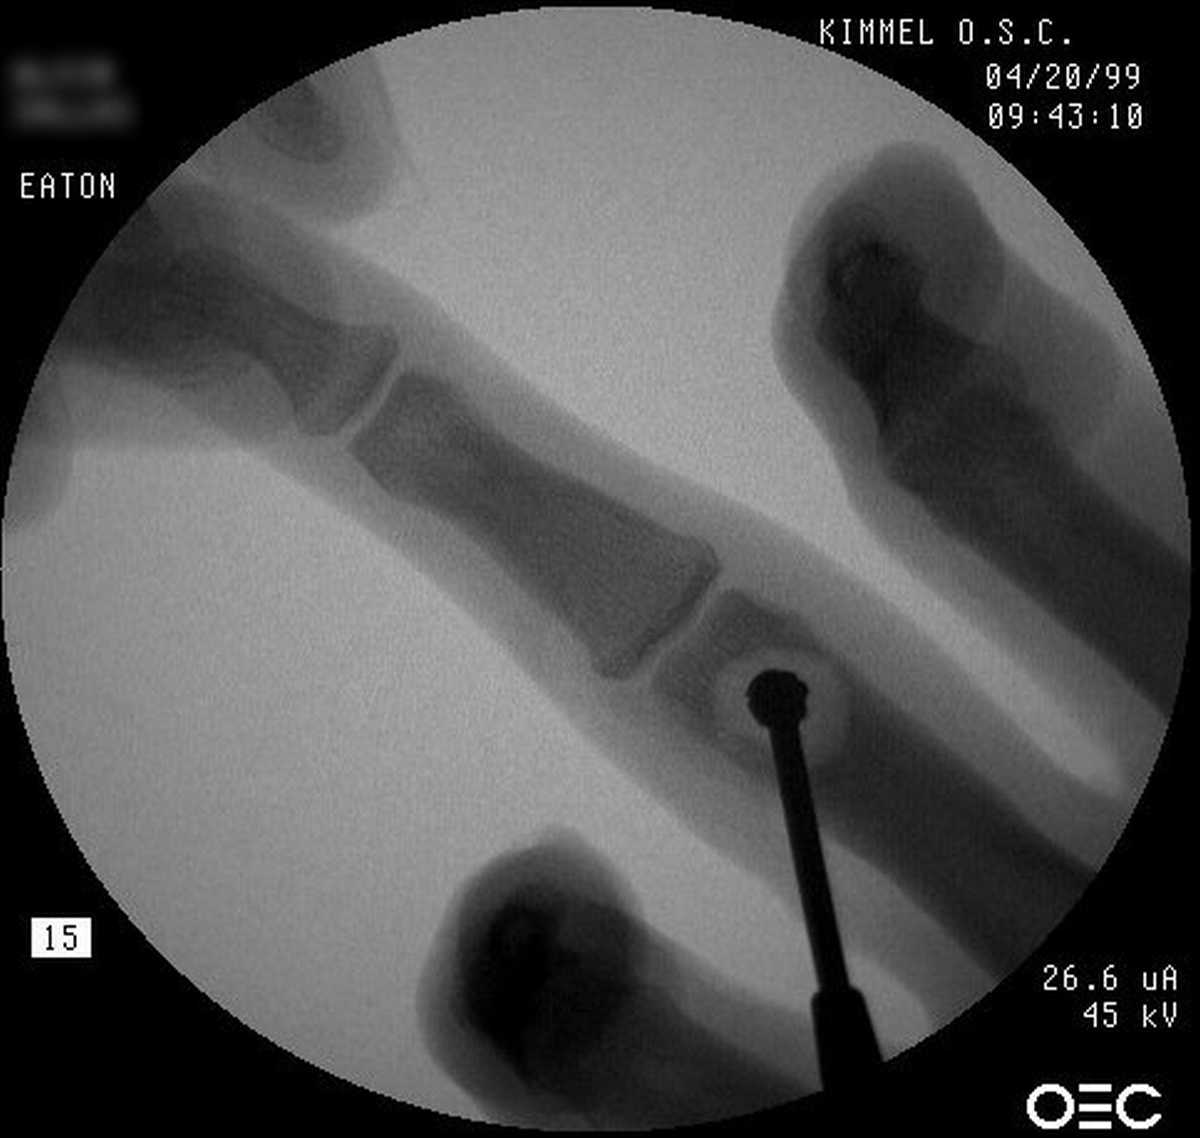

| The tumor was resected

using a dorsal tendon splitting exposure. |

| Debridement was continued

until normal counts were demonstrated . This left a thin

cortical shell which was reconstructed with a corticocancellous graft

from the distal radius. |